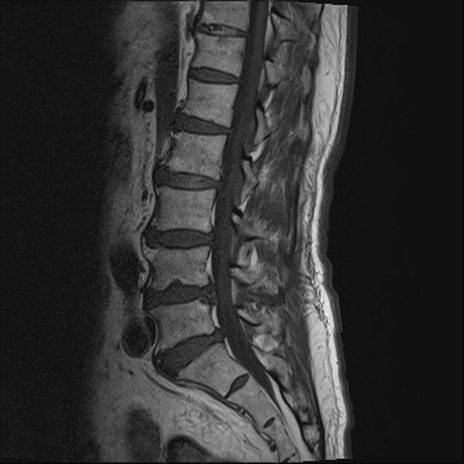

【整形】TIPS症例2 腰椎MRI T1WI(矢状断像)

【症例】70歳代男性

【主訴】左下肢痛

【現病歴】2週間前くらいから腰痛、左下肢痛あり。左臀部から大腿、下腿外側のしびれが常時ある。歩行とともに同部位の痛みあり。

【身体所見】Lasegue70-/60+、Bragard-/±、PTR ±/±、ATR -/-、IP 5/5、TA 5/4、TS 5/5、EHL 右第1足趾なし/3、FHL 5/5、hypersthesia(-)、足背動脈触知良好

異常所見と診断は?